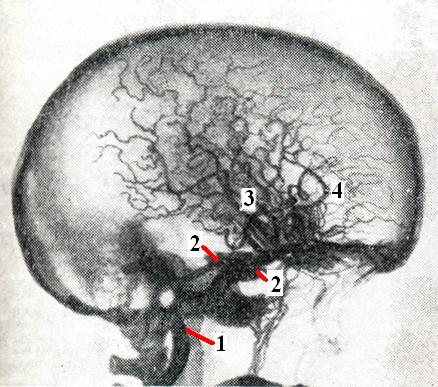

Рис. 1.

Каротидно-кавернозное соустье: 1 - лнутренняя сонная артерия; 2 — кавернозный синус; 3 — средняя мозговая артерия; 4 — передняя мозговая артерия.